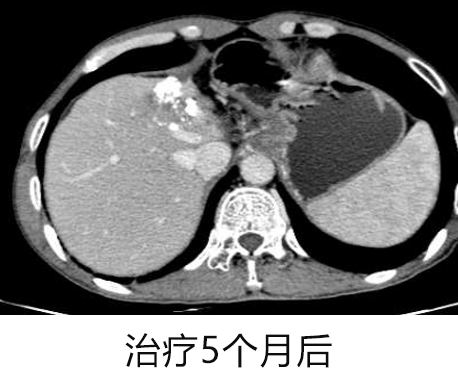

治疗前与治疗 5 个月后 CT 对比:

复查 CT 结果显示 肝脏左叶原发性肝癌介入栓塞术后病灶范围进一步缩小,AFP 指标也呈下降趋势。

在之后的 MDT 讨论结果中,普外科提出以下治疗建议:

1. 患者经过有效的转化治疗,出现了局部治疗的机会,建议进行积极的外科手术或消融治疗。

2. 继续维持性治疗,继续口服索拉非尼+PD1。 患者基于自身的身体和经济状况,选择了肝脏消融治疗,并继续口服索拉非尼+PD1 进行维持治疗。